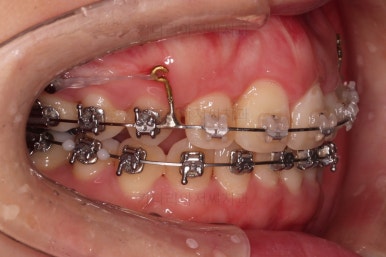

미니스크류를 적절히 사용해서 부정교합도 맞추고 입매도 약간 들어가게 혹은 너무 들어가지 않게 조절해 주고요.

치열의 경사 등등도 조절해 줍니다.

부산부정교합이긴 하지만 애초에 입매가 많이 나쁘진 않았기 때문에 자칫하면 입이 너무 들어갈 수 있어 중간중간 환자분과 상의하여 너무 들어가지 않게끔 조절해 줍니다.

적절하게 틈도 다 모아주고요.